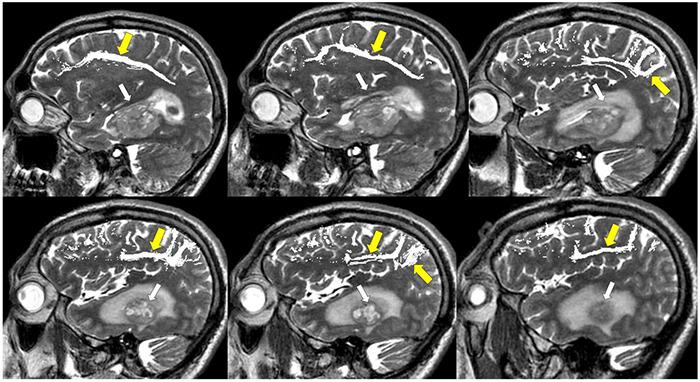

Management of gliomas following initial diagnosis requires thoughtful presurgical planning followed by regular imaging to monitor treatment response and survey for new tumor growth. Traditional MR imaging modalities such as T1 post-contrast and T2-weighted sequences have long been a staple of tumor diagnosis, surgical planning, and post-treatment surveillance. While these sequences remain integral in the management of gliomas, advances in imaging techniques have allowed for a more detailed characterization of tumor characteristics. Advanced MR sequences such as perfusion, diffusion, and susceptibility weighted imaging, as well as PET scans have emerged as valuable tools to inform clinical decision making and provide a non-invasive way to help distinguish between tumor recurrence and pseudoprogression. Furthermore, these advances in imaging have extended to the operating room and assist in making surgical resections safer. Nevertheless, surgery, chemotherapy, and radiation treatment continue to make the interpretation of MR changes difficult for glioma patients. As analytics and machine learning techniques improve, radiomics offers the potential to be more quantitative and personalized in the interpretation of imaging data for gliomas. In this review, we describe the role of these newer imaging modalities during the different stages of management for patients with gliomas, focusing on the pre-operative, post-operative, and surveillance periods. Finally, we discuss radiomics as a means of promoting personalized patient care in the future.

胶质瘤初诊后的管理需要进行周全的术前规划,随后定期进行影像学检查,以监测治疗反应并探查新的肿瘤生长情况。传统的磁共振成像(MR)模式,如T1增强序列和T2加权序列,长期以来一直是肿瘤诊断、手术规划及治疗后监测的主要手段。虽然这些序列在胶质瘤的管理中仍不可或缺,但成像技术的进步使得对肿瘤特征的刻画更加详细。诸如灌注成像、扩散加权成像、磁敏感加权成像等先进的MR序列,以及正电子发射断层显像(PET)扫描,已成为指导临床决策的重要工具,并提供了一种非侵入性方法,有助于区分肿瘤复发和假性进展。此外,这些成像技术的进步已延伸至手术室,有助于使手术切除更安全。尽管如此,手术、化疗和放疗仍使胶质瘤患者的MR图像变化解读变得困难。随着分析和机器学习技术的进步,放射组学在解读胶质瘤成像数据方面具有实现更具定量性和个性化的潜力。在本综述中,我们描述了这些更新的成像模式在胶质瘤患者不同管理阶段的作用,重点关注术前、术后及监测期。最后,我们讨论放射组学作为未来促进个性化患者护理的一种手段。